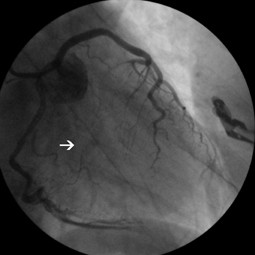

Fig. 4

Vidoe 2. Thrombolysis In Myocardial Infarction -3 flow was ensured (avi 1,1MB)